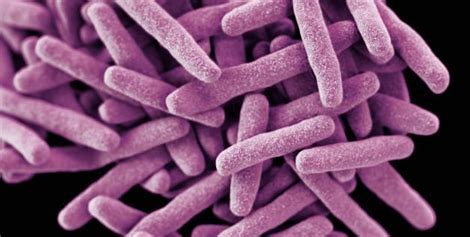

ക്ഷയരോഗം, പ്രധാനമായും ശ്വാസകോശത്തെ ബാധിക്കുന്ന ഒരു ബാക്ടീരിയൽ ഇൻഫെക്ഷൻ ആണ്. എന്നാൽ ഇത് ശരീരത്തിന്റെ മറ്റ് ഭാഗങ്ങളെയും ബാധിക്കാം. ഇത് ഒരു വ്യക്തിയിൽ നിന്ന് മറ്റൊരാളിലേക്ക് വായു മാർഗ്ഗം പകരാവുന്ന രോഗമാണ്.